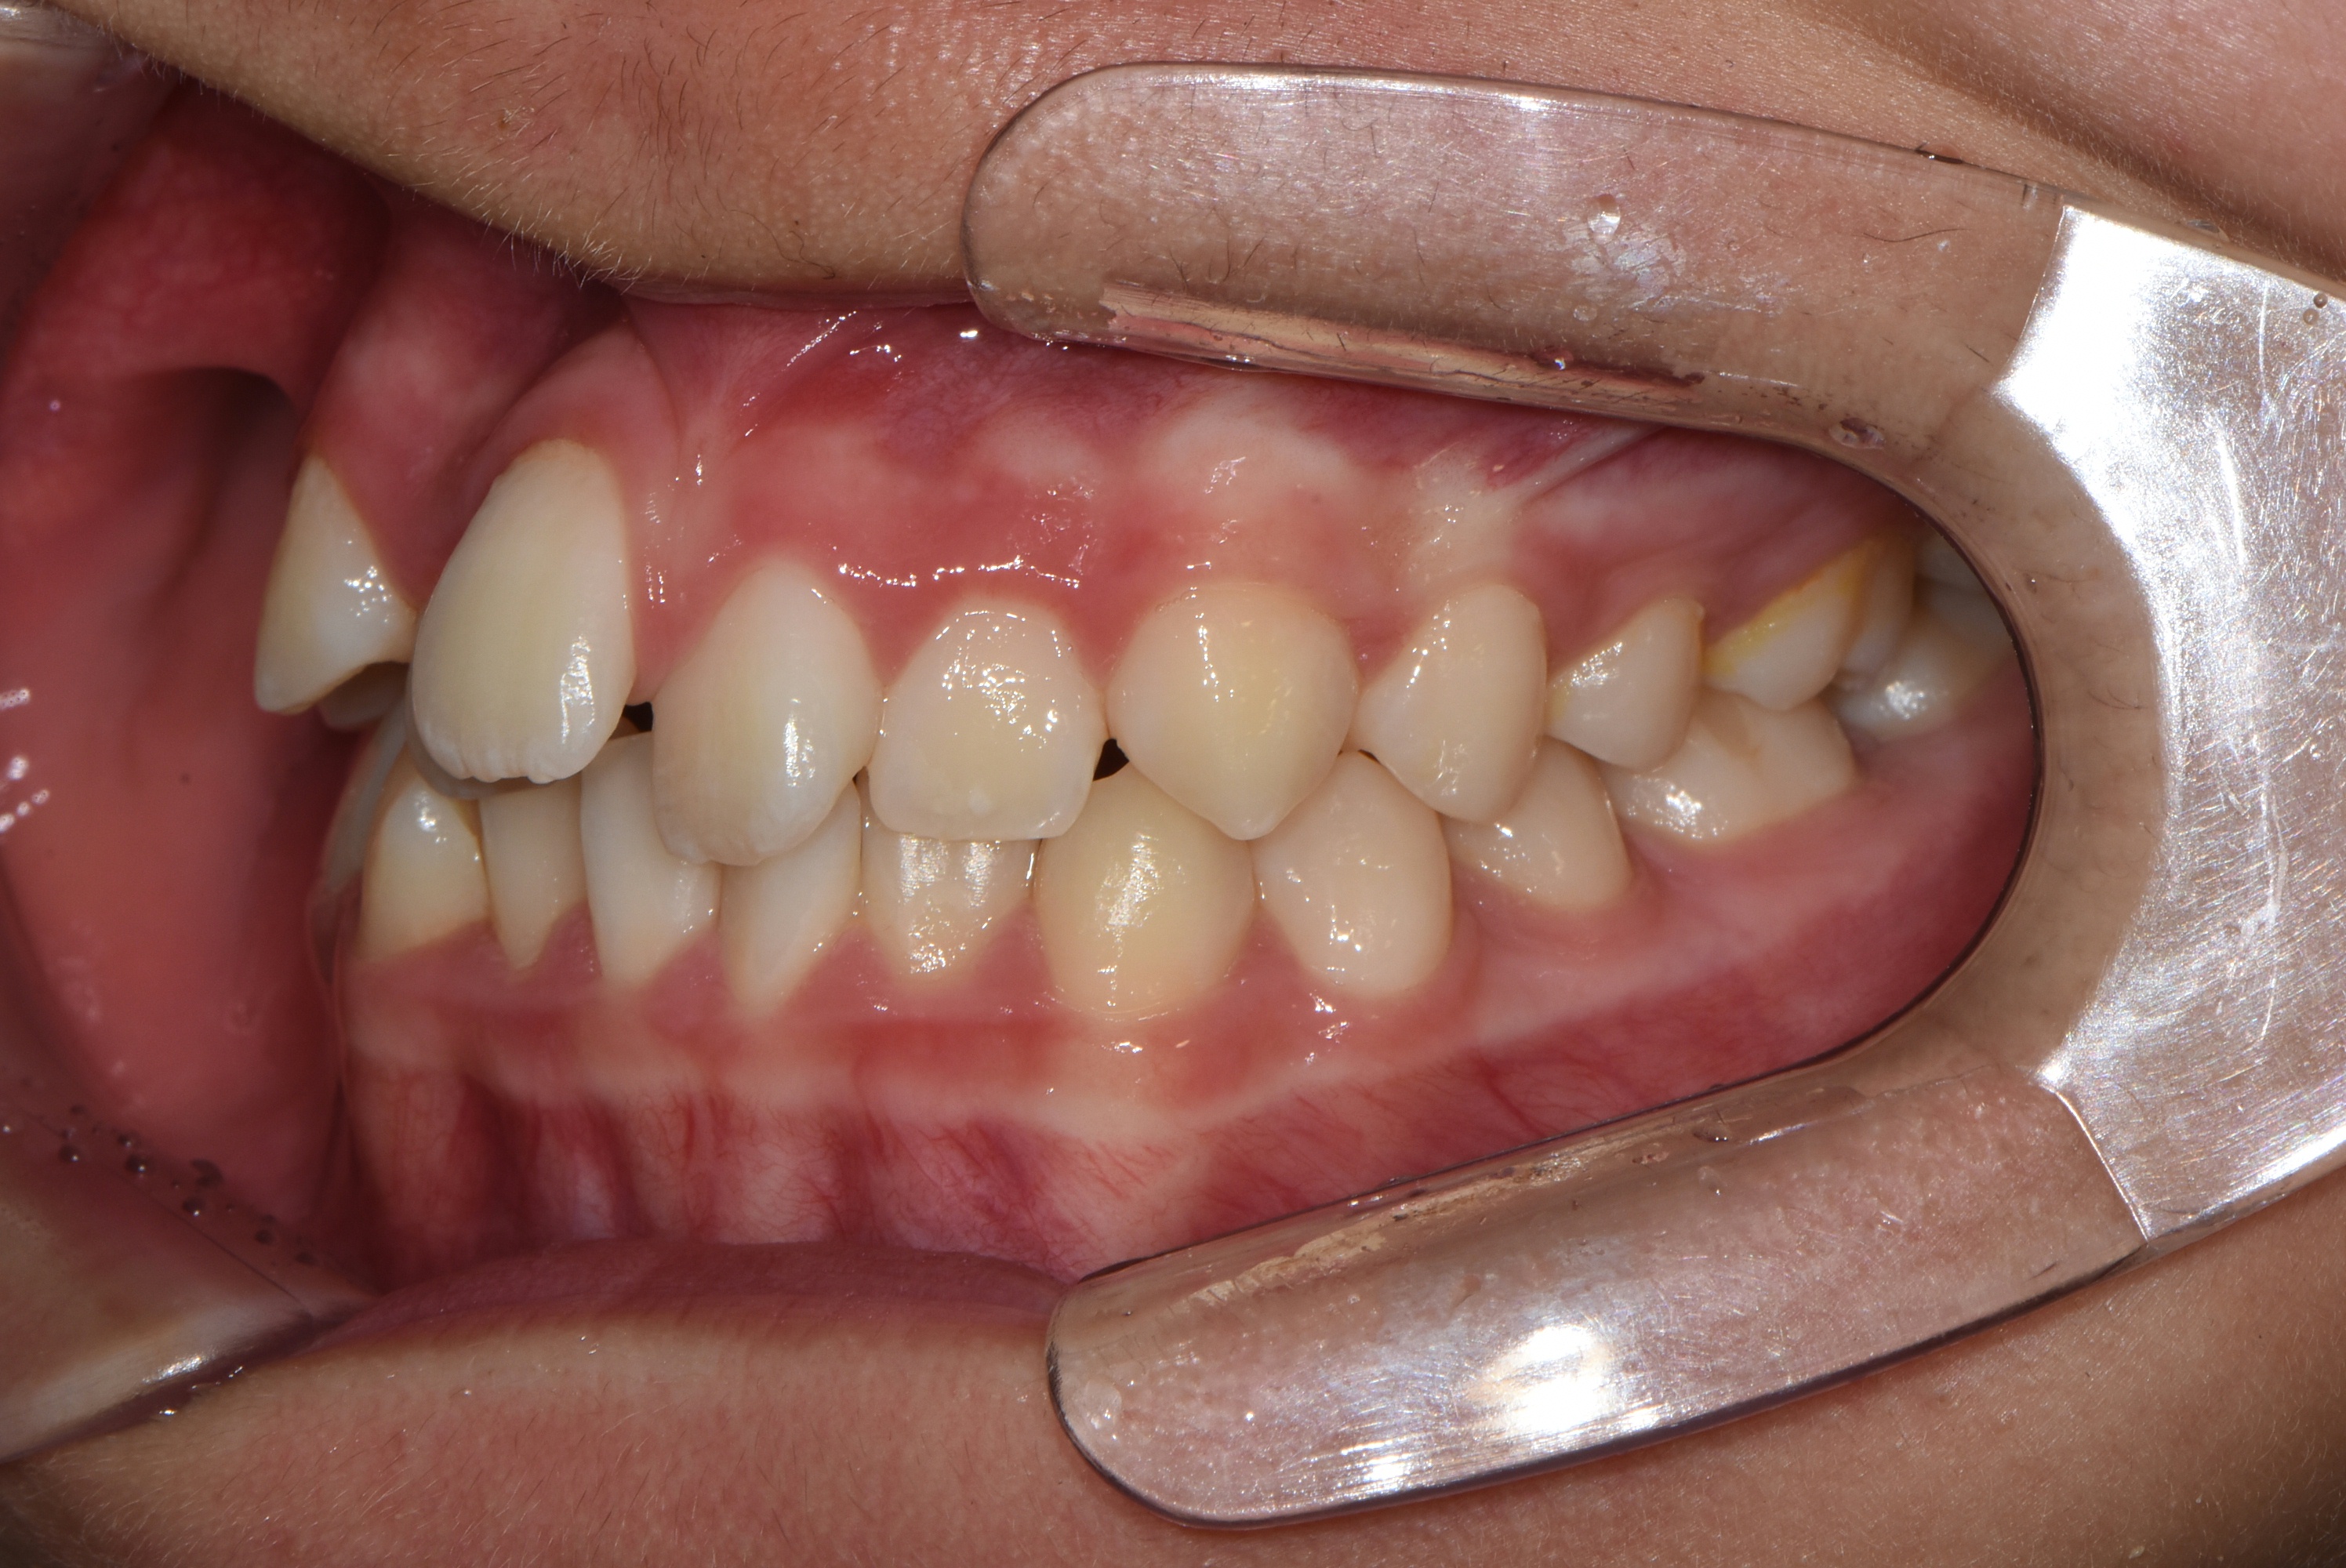

치료 전 사진입니다.